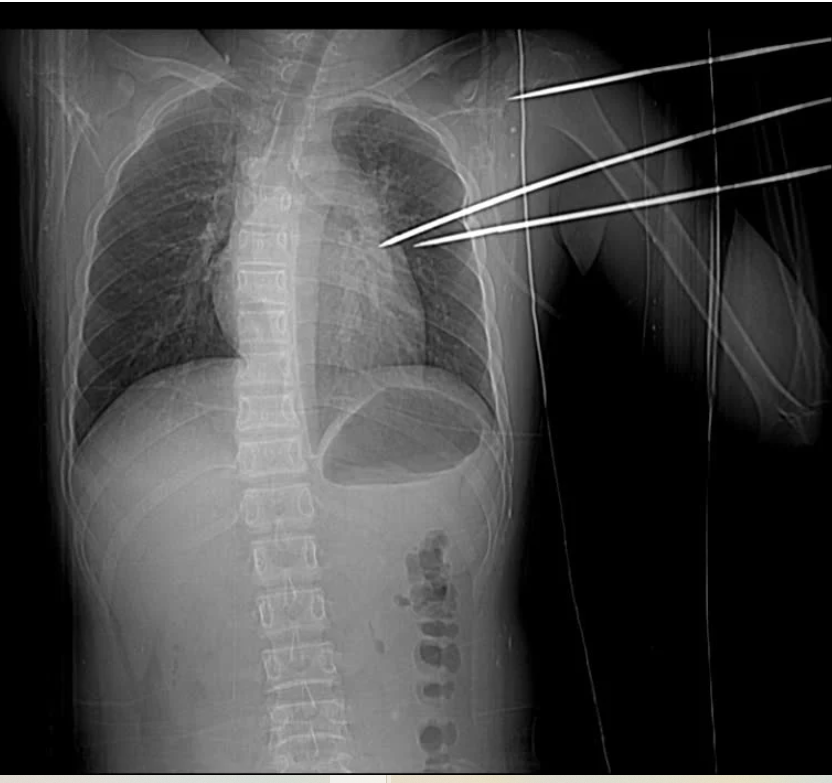

Bệnh nhân nhập viện với dị vật kim loại sắc nhọn, dạng đinh ba tự chế, đâm thẳng từ phía sau vai trái, xuyên sâu vào lồng ngực.

Khi nhập viện, bệnh nhân trong tình trạng tỉnh táo, mạch và huyết áp tạm thời ổn định. Tuy nhiên, kết quả thăm khám nhanh chóng cho thấy tình hình nguy cấp: một dị vật kim loại sắc nhọn, dạng đinh ba tự chế, đâm thẳng từ phía sau vai trái, xuyên sâu vào lồng ngực.

Dị vật kim loại sắc nhọn, dạng đinh ba tự chế, đâm từ phía sau vai trái, xuyên sâu vào lồng ngực, gây tổn thương phổi và tim của bệnh nhân.

Hình ảnh chụp X-quang và CT cho thấy dị vật không chỉ xuyên qua mặt sau vai trái mà còn xuyên qua mô thùy trên phổi trái, đâm vào thành bên thất trái của tim, gây tràn máu màng tim – một tổn thương cực kỳ nghiêm trọng.